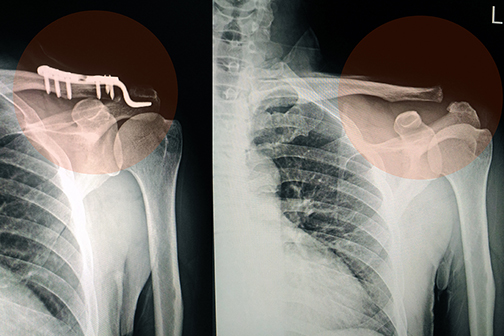

Orthopaedics faculty at LSU Health New Orleans participated in a study comparing two antisepsis aqueous solutions in reducing the risk of infection in patients requiring surgery for open fractures. In the largest known randomized-controlled trial, the research team found that contrary to current international recommendations, chlorhexidine gluconate was not superior to povidone-iodine in an alcohol or aqueous solution in preventing surgical site infection. More